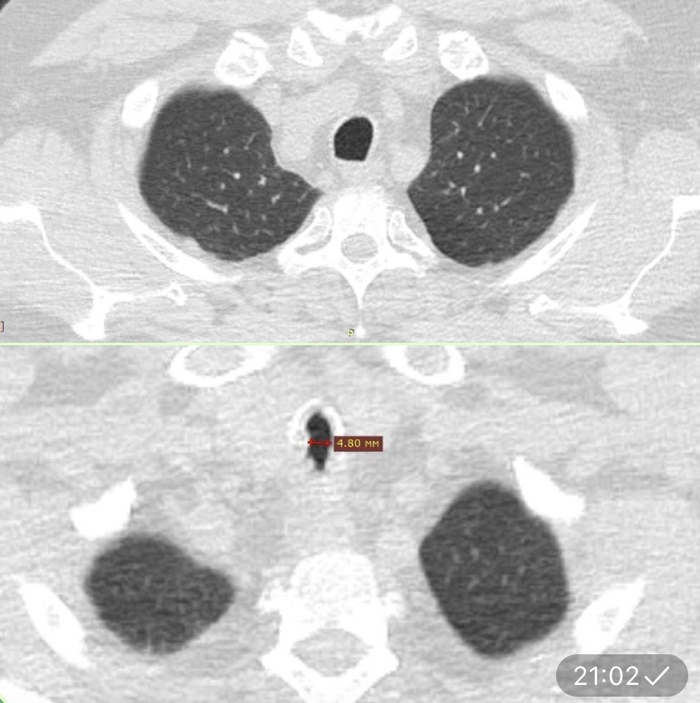

Компьютерная томография. Вверху неизмененная часть трахеи. Внизу щелевидный стеноз трахеи до 4 мм. Ниже видео - эндосокпическая картина рубцового стеноза (бронхоскопия).